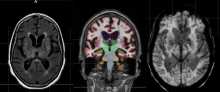

Global magnetic resonance imaging (MRI) safety firm Metrasens recently conducted a survey in which 36 percent of 162 MRI professionals admitted they are not compliant with the Revised Requirements for Diagnostic Imaging Services. The standards were released in July of 2015 by the Joint Commission, a non-profit organization that accredits and certifies more than 21,000 healthcare organizations and programs in the United States.